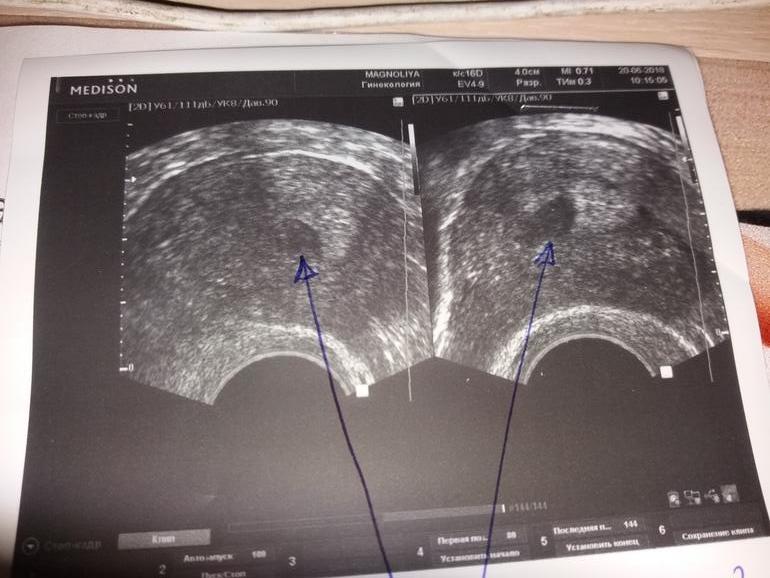

Такой вопрос. Была на узи малого таза ( направила эндокринолог исключить СПКЯ) там все Хорошо, но есть гипоэхогенное образование 9.1 мм.

Это не беременность. Полость матки не расширена, видна средняя линия смыкания листов эндометрия. Это пристеночное образование либо субсерозная миома, либо полип. Скорее всего, первое